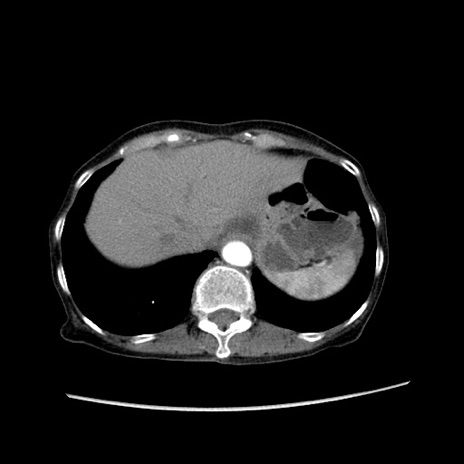

症例25(横断像)

【症例】80歳代女性

【主訴】胸のつかえ感

【現病歴】約9時間前に食後から胸のつかえた感じあり、嘔吐あり、来院。

【既往歴】胃癌(全摘)、胆摘、虫垂炎

【身体所見】心窩部に圧痛あり、反跳痛なし。

【データ】WBC 5700、CRP 0.05